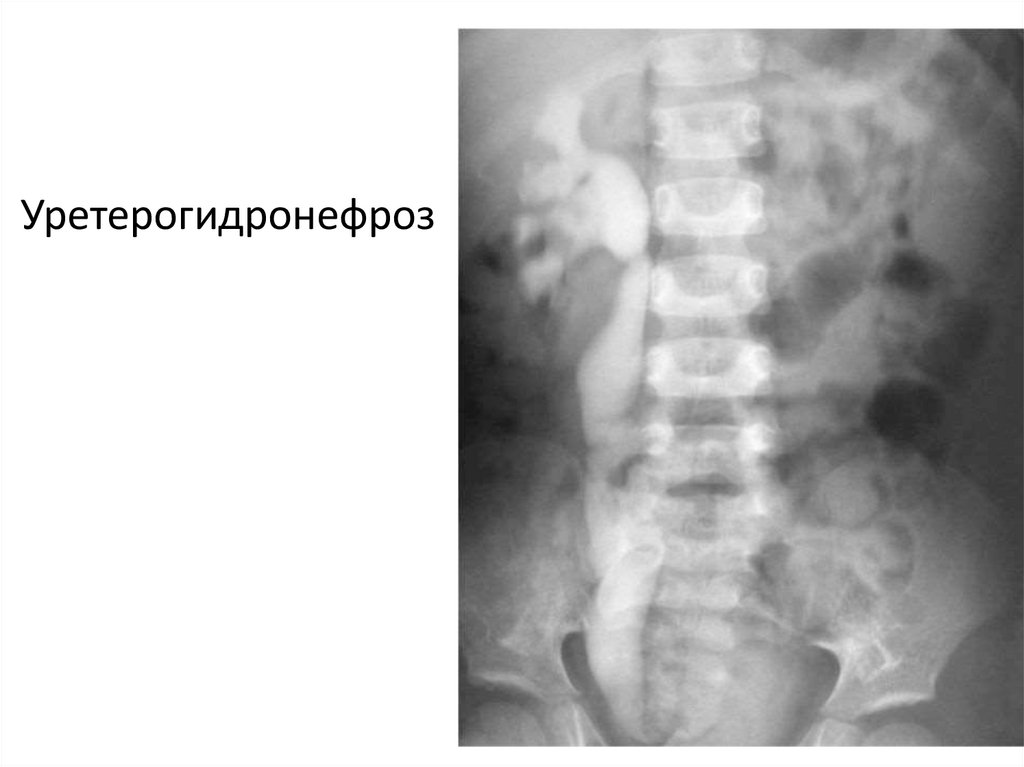

Уретерогидронефроз

19.